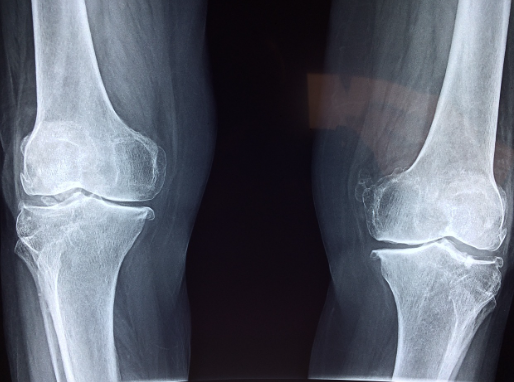

예를 들어 손목 관절, 팔꿈치 관절, 무릎 관절, 골반 관절 등이 있습니다. 이 관절들은 각각의 구조와 기능에 따라 다양한 움직임을 수행하며 운동과 일상 생활에서 중요한 역할을 합니다. 관절 내 연골은 지속적으로 마모되고 대체되며 이런 과정이 손상되면 관절염이 발생할 수 있습니다.

관절염은 여러 가지 원인으로 인해 관절에 염증이 생겨 통증과 기능 저하를 일으키는 상황입니다. 관절염의 종류는 다양하며 정확한 진단과 치료가 필요합니다. 관절 통증과 관절염은 다른 것이며 관절 통증이 있더라도 모든 경우가 관절염은 아닙니다. 관절염은 치료와 병의 경과가 다양하므로 정확한 진단과 치료가 중요합니다.